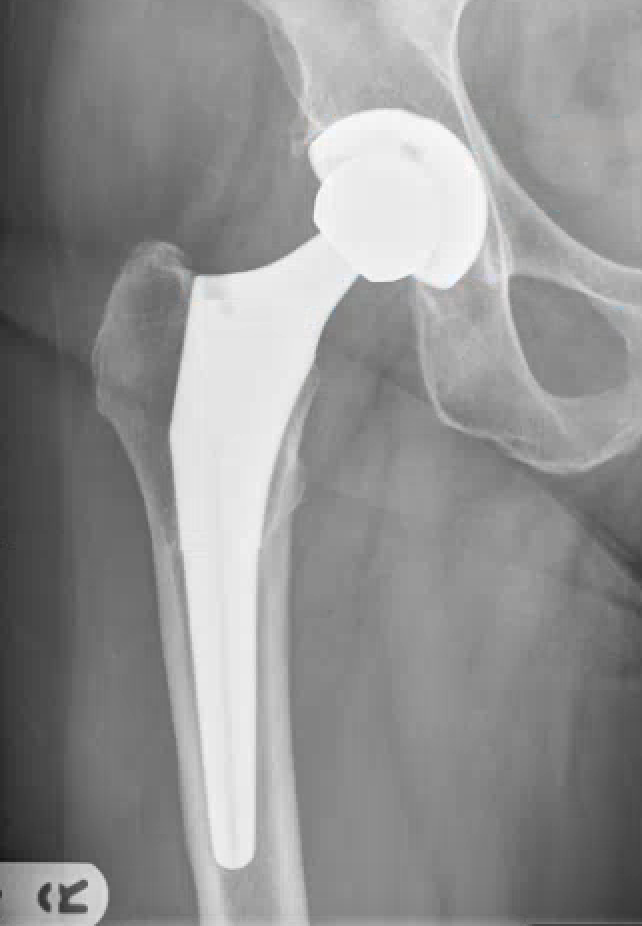

For this 74-year-old woman:

- Hip Joint => All is well. Phew..

- Hip Joint => Reassure. Stay active. Maintain good bodyweight. Next check 5 years.